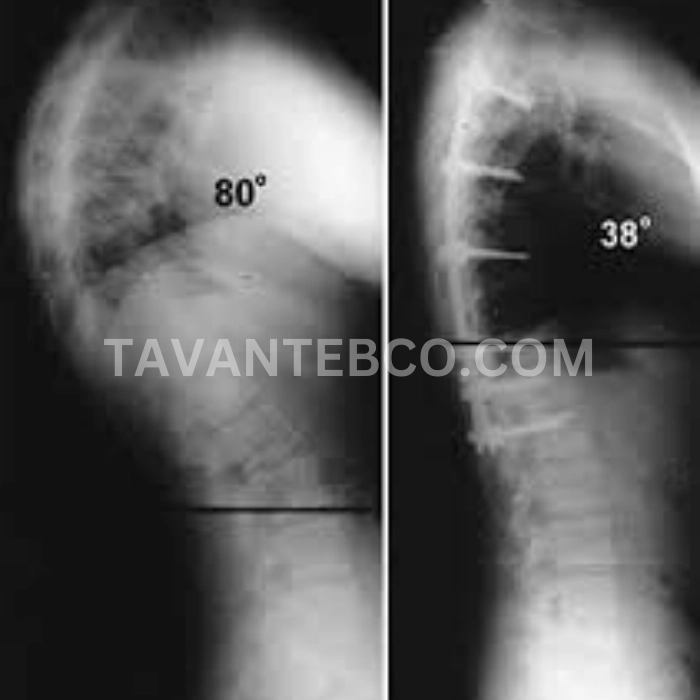

در موارد شدید کایفوز که زاویه انحنا بیش از ۷۰ درجه باشد یا همراه با مشکلات جدی مانند درد مداوم، فشار روی اعصاب، اختلالات تنفسی و محدودیت شدید حرکتی باشد، معمولاً جراحی بهعنوان گزینه درمانی در نظر گرفته میشود. در این روش با استفاده از پیچها و میلههای مخصوص، ستون فقرات در وضعیت مناسبتر تثبیت میگردد. جراحی بیشتر برای موارد پیشرفته توصیه میشود و نیازمند مراقبت و توانبخشی پس از عمل است.

پزشک ارتوپد یا متخصص ستون فقرات با معاینه بالینی و تصویربرداری (رادیوگرافی ساده، MRI یا CT اسکن) میتواند زاویه انحنای ستون فقرات را اندازهگیری کند. معمولاً اگر زاویه انحنا بالای ۴۵ درجه باشد، فرد دچار کایفوز محسوب میشود. تشخیص زودهنگام قوز کمر اهمیت زیادی دارد. متخصص ارتوپد یا ستون فقرات از روشهای زیر استفاده میکند:

عکسبرداری (X-ray): برای اندازهگیری زاویه انحنا (بیش از ۴۵ درجه نشانه کایفوز است)